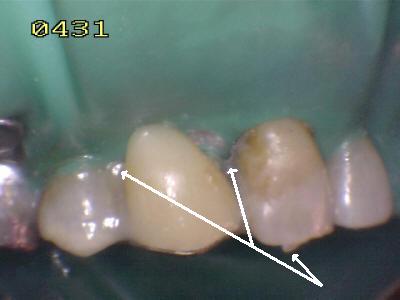

Cementado con la goma dique.  Observe los excesos de cemento de resina de curado dual (flechas blancas)